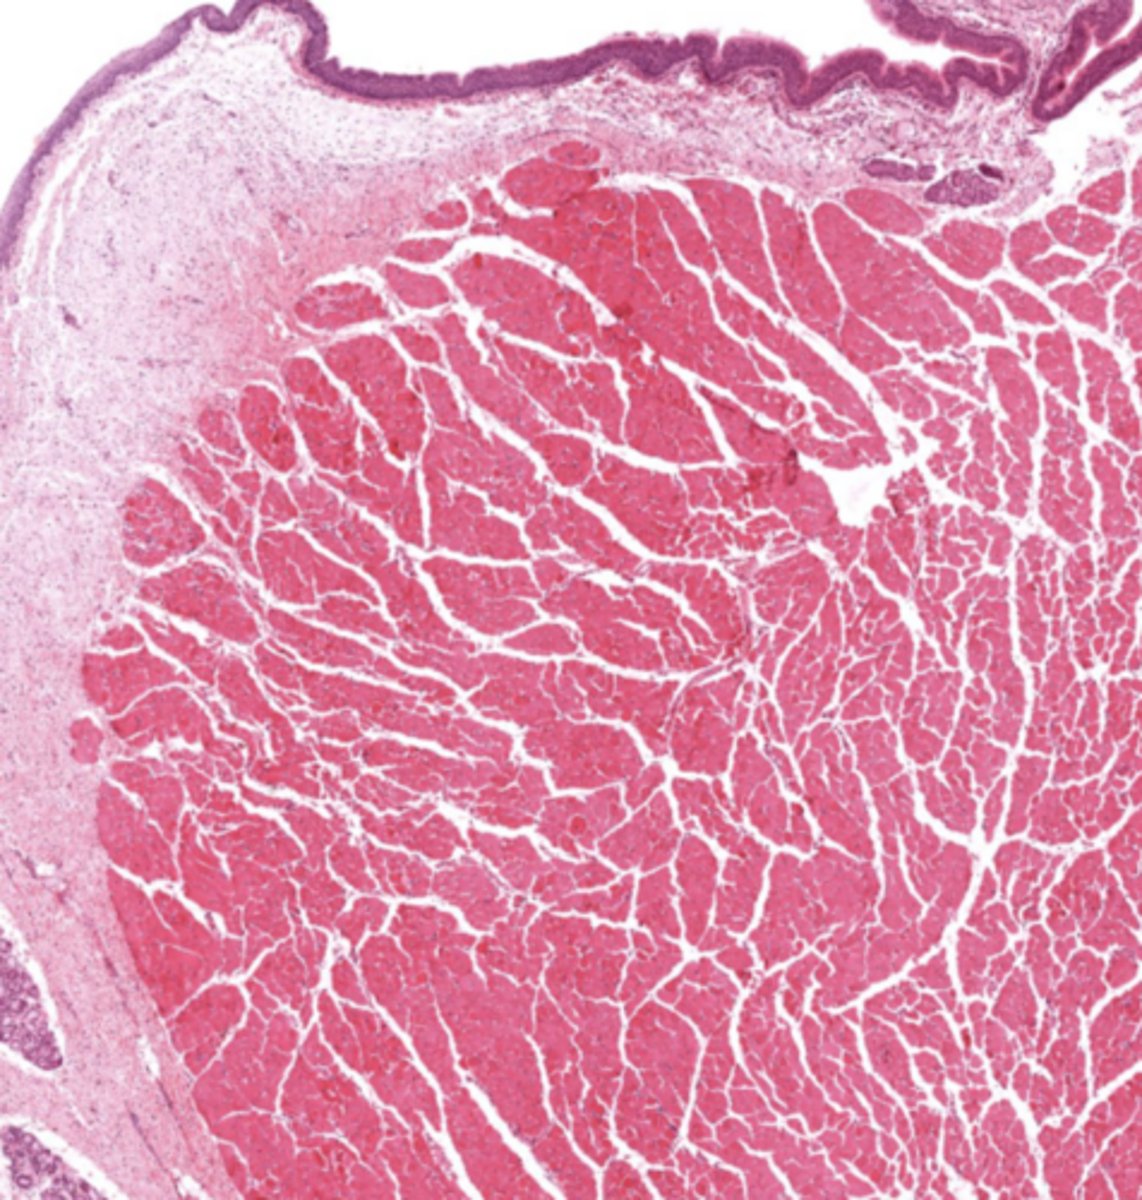

What muscle is found in the true vocal cords?

Vocalis muscle (skeletal muscle).

What forms the vocal ligament?

A band of elastic fibers.

What epithelium lines the true vocal cords? and why is it this specific epithelium?

Stratified squamous non-keratinized epithelium

so we can speak if we had any other lining the voice will be distorted

Why is Reinke's space clinically important?

No lymphatic vessels -> Reinke's edema.

True cords of the larynx

Identify the image